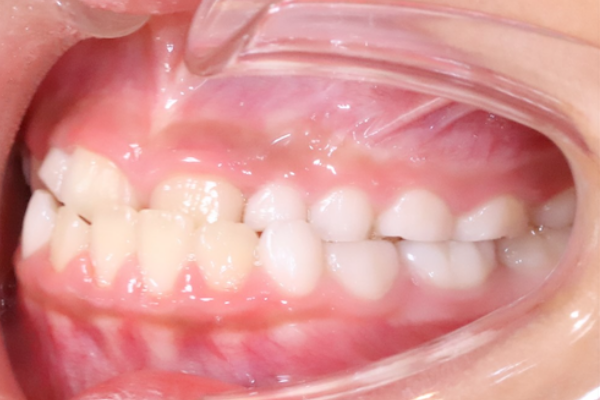

子供の受け口(反対咬合・下顎前頭)の矯正治療例

9歳 男の子

上下反対の噛み合わせでしゃくれて見える

下顎前突

プレート(拡大症)にて矯正治療を行った

1年半

・決められた範囲のみネジを回す必要がある

・装着時間を守らないと効果が得られない

検査:44,000円(税込)

装置:385,000円(税込)

合計:429,000円(税込)